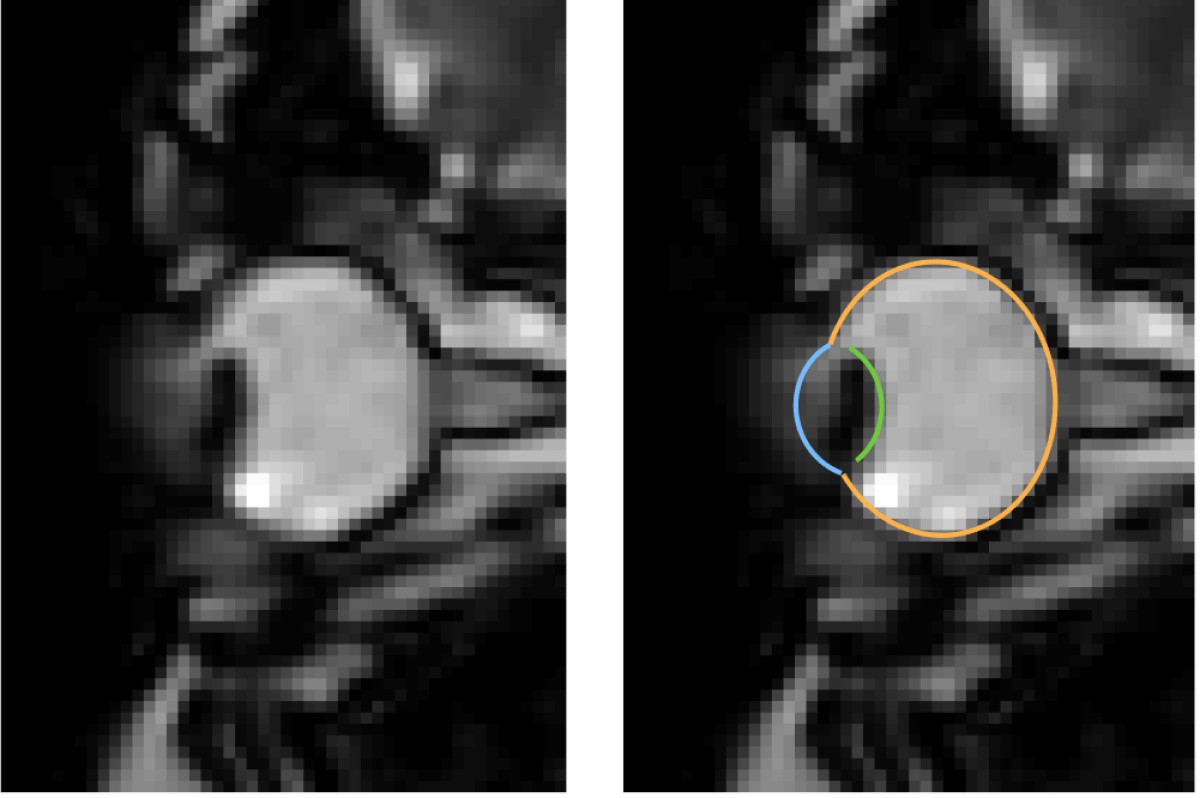

MRI images of eye movements during blinking: The eye is pulled back into the eye socket. The left image shows only the dynamic MRI data, the right image additionally shows the segmentation of the eye by the MREyeTrack. The photo corner consisting of six images shows the eye movement.© WWU - Johannes Kirchner

Eye movements are typically measured using eye-trackers, which are high speed cameras that film pupil position.” We were able to develop a method that captures eye movements in unprecedented temporal resolution using real-time MRI. Using this new method, we could show that the whole eyeball is being pulled back into the eye socket during a blink“, explains author Johannes Kirchner, research assistant at the Institute of Psychology at Münster University. The scientists from the University of Münster developed the method with co-author Prof. Tamara Watson from Western Sydney University.

MRI is a relatively slow procedure, the temporal resolution usually ranges between seconds or minutes. Eye movements on the other hand are fast and typically last only a few dozen milliseconds. Recent technological advances allowed the recording of 2-D MR images at a resolution of up to 20 milliseconds. Those ultrafast MR sequences were initially developed for cardiac imaging and haven’t been applied to the recording of eye movements. “We could reach a temporal resolution of 35 milliseconds. Total scan duration of only a few minutes already leads to the acquisition of over 10000 images. For actual eye-tracking, a fully automatic segmentation algorithm to analyse these images was needed”, explains co-author Prof. Markus Lappe, professor for cognitive neuroscience at the Institute of Psychology at the University of Münster. “With ‘MREyeTrack’ we have developed such a segmentation algorithm, which allows the fully-automated analysis of eye position and orientation in every single image.”